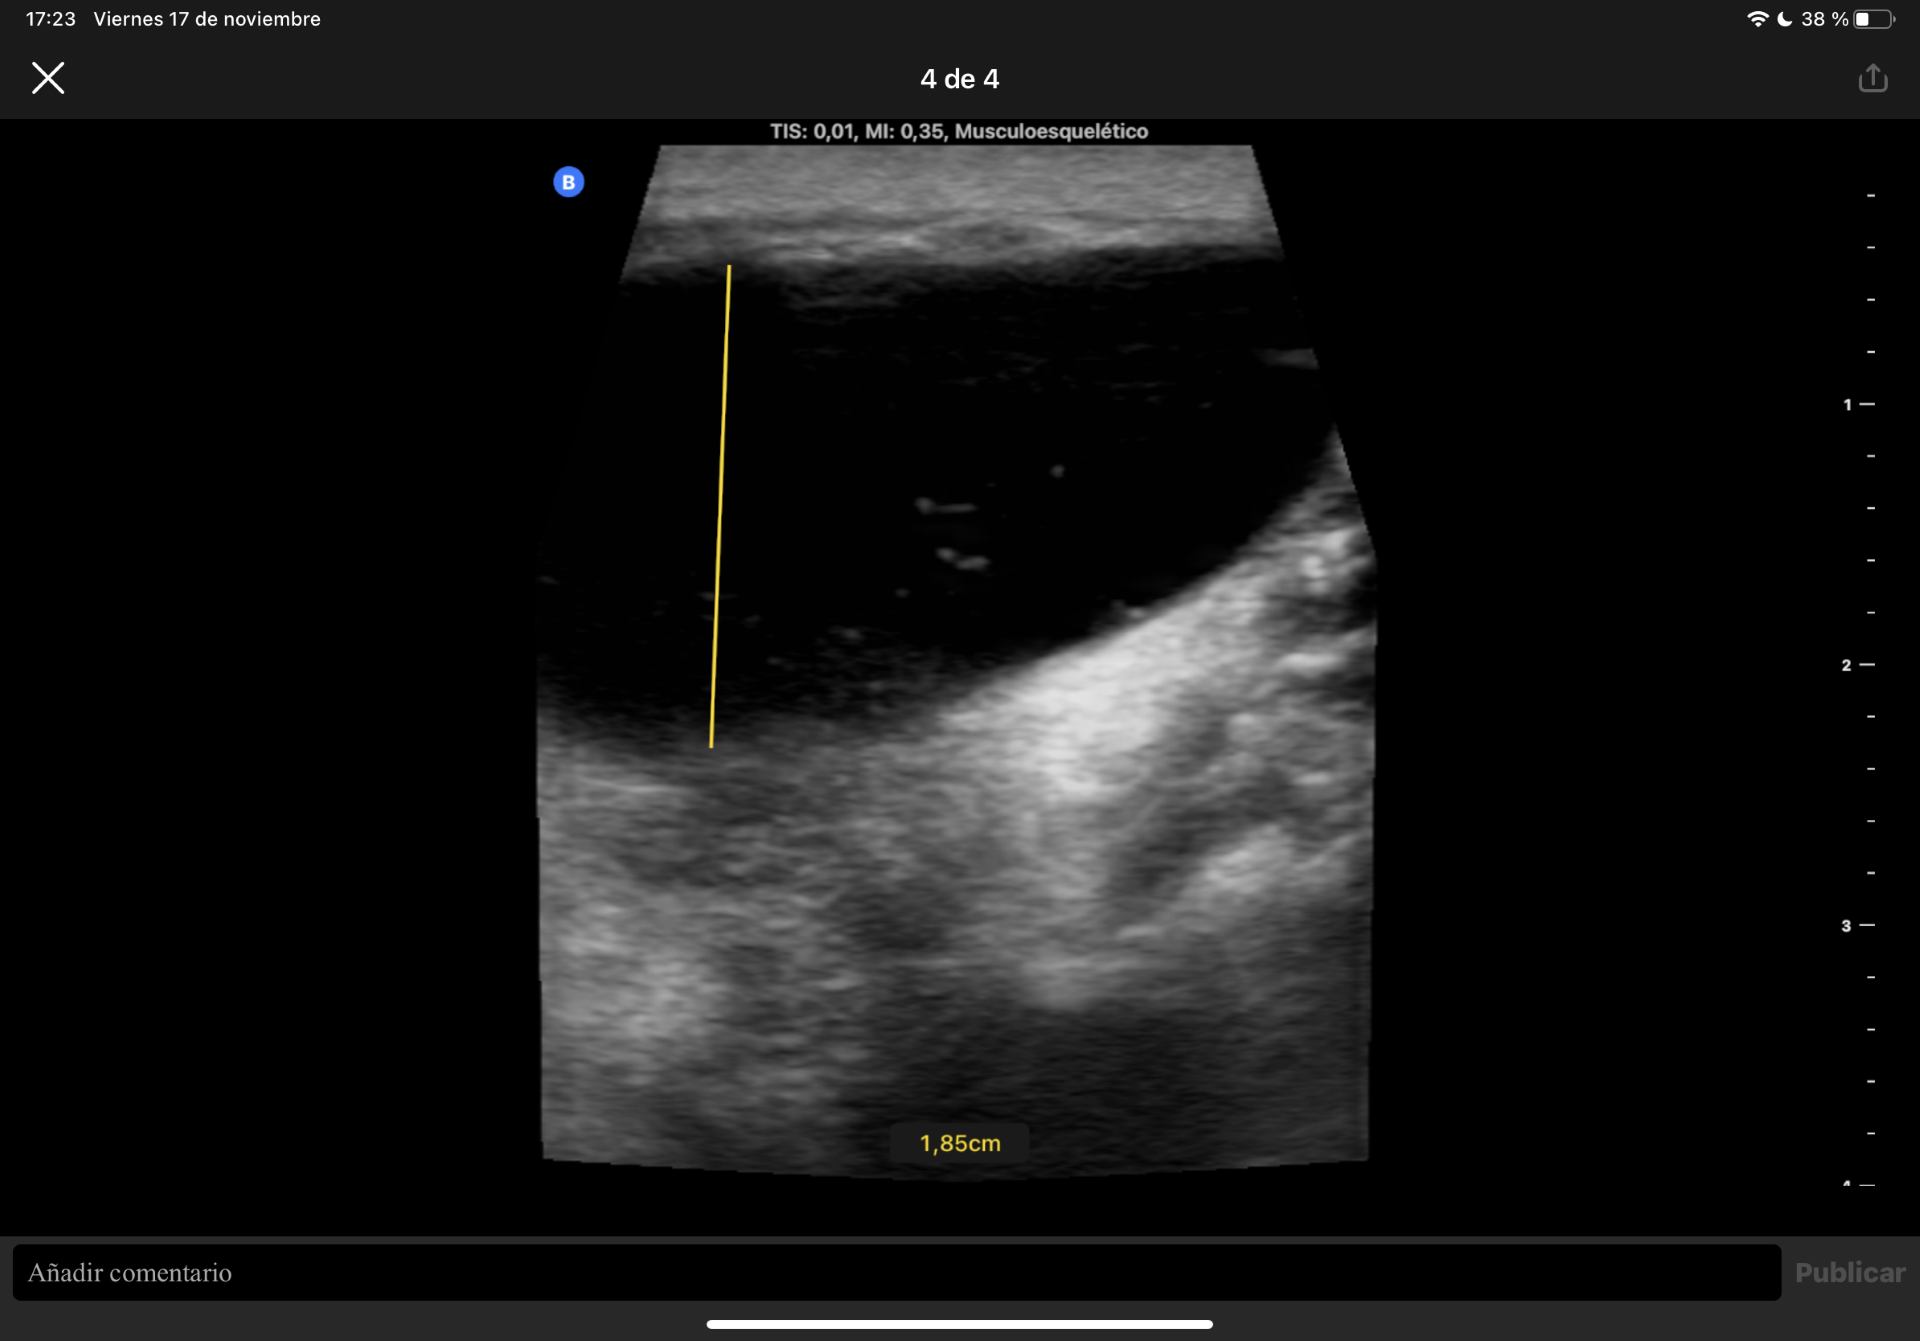

Ante la sospecha de quiste sinovial se realiza Ecografía músculo esquelética en consulta.

Hallazgos ecográficos

Difícil acceso por las forma de la masa. Se observa en plano dérmico lesión sin pared de 1,85 cm en su mayor altura, aneicoica con flóculos en su interior. No parece depender de la articulación del hombro ni la acromionclavicular, no se aportan más medidas por salirse de la ventana del ecógrafo.